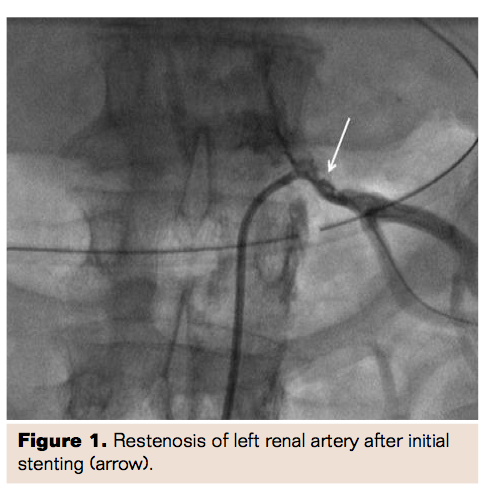

During the current admission, the patient was diuresed, which resulted in some improvement of his symptoms and a dobutamine stress echocardiogram was performed, which showed posterior wall hypokinesis with stress. Ten days after admission, a diagnostic catheterization procedure was performed, which showed a lesion in the obtuse marginal vessel and pseudoaneurysm at the site of the left renal artery stent with multiple fractures of stent struts (Figure 2). An abdominal computed tomography angiography was performed to better define the pseudoaneurysm, which showed a circumferential pseudoaneurysm at the area of the stent without a neck and with thin walled encapsulation (Figures 3 and 4).

Here we discuss a case with renal artery stenosis causing severe uncontrolled hypertension and flash pulmonary edema. The patient showed an immediate abatement of symptoms after bilateral renal artery stenting. However this was followed by restenosis of the left renal artery stent and subsequent balloon angioplasty. Thereafter it was discovered that the patient had stent fractures with the development of a pseudoaneurysm. It was interesting to note that the pseudoaneurysm did not have a neck as ordinarily seen, but was all around the proximal artery and contained by a thin wall of tissue. This was likely due to the stent fracture causing a perforation leading to a leak contained by the surrounding tissue. The patient’s local symptoms had remained stable, but he had uncontrolled hypertension and multiple admissions for pulmonary edema.